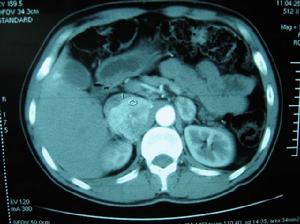

B型超聲和CT掃描對嗜鉻細胞瘤的診斷準確率高,而且無創傷,有條件應作為首選檢查方法。1.5cm以上的腫瘤經CT掃描可準確定位,小於1cm者困難些,需結合其他檢查綜合分析。CT掃描除能對腫瘤進行定位和測量大小外,還可根據腫瘤邊界等情況,判斷其有否浸潤、轉移等,以利選取合適的治療方法。腔靜脈分段取血定位檢查,對嗜鉻細胞瘤定位,尤其對體積小的腫瘤、異位腫瘤或其他檢查未能定位的腫瘤,有較高的價值,可給CT掃描提供一定的參考。131 I-間位碘苄胍(131 I-MIBG)造影,對嗜鉻細胞瘤的診斷及定位提供了重要方法。其原理是MIBG在化學結構上類似去甲腎上腺素,能被腎上腺髓質和嗜鉻細胞瘤攝取。故對嗜鉻細胞瘤檢查有特異性,能鑑別腎上腺或腎上腺以外其他部位的腫瘤是否為嗜鉻細胞瘤。具有安全、特異和準確率高的優點。治療措施